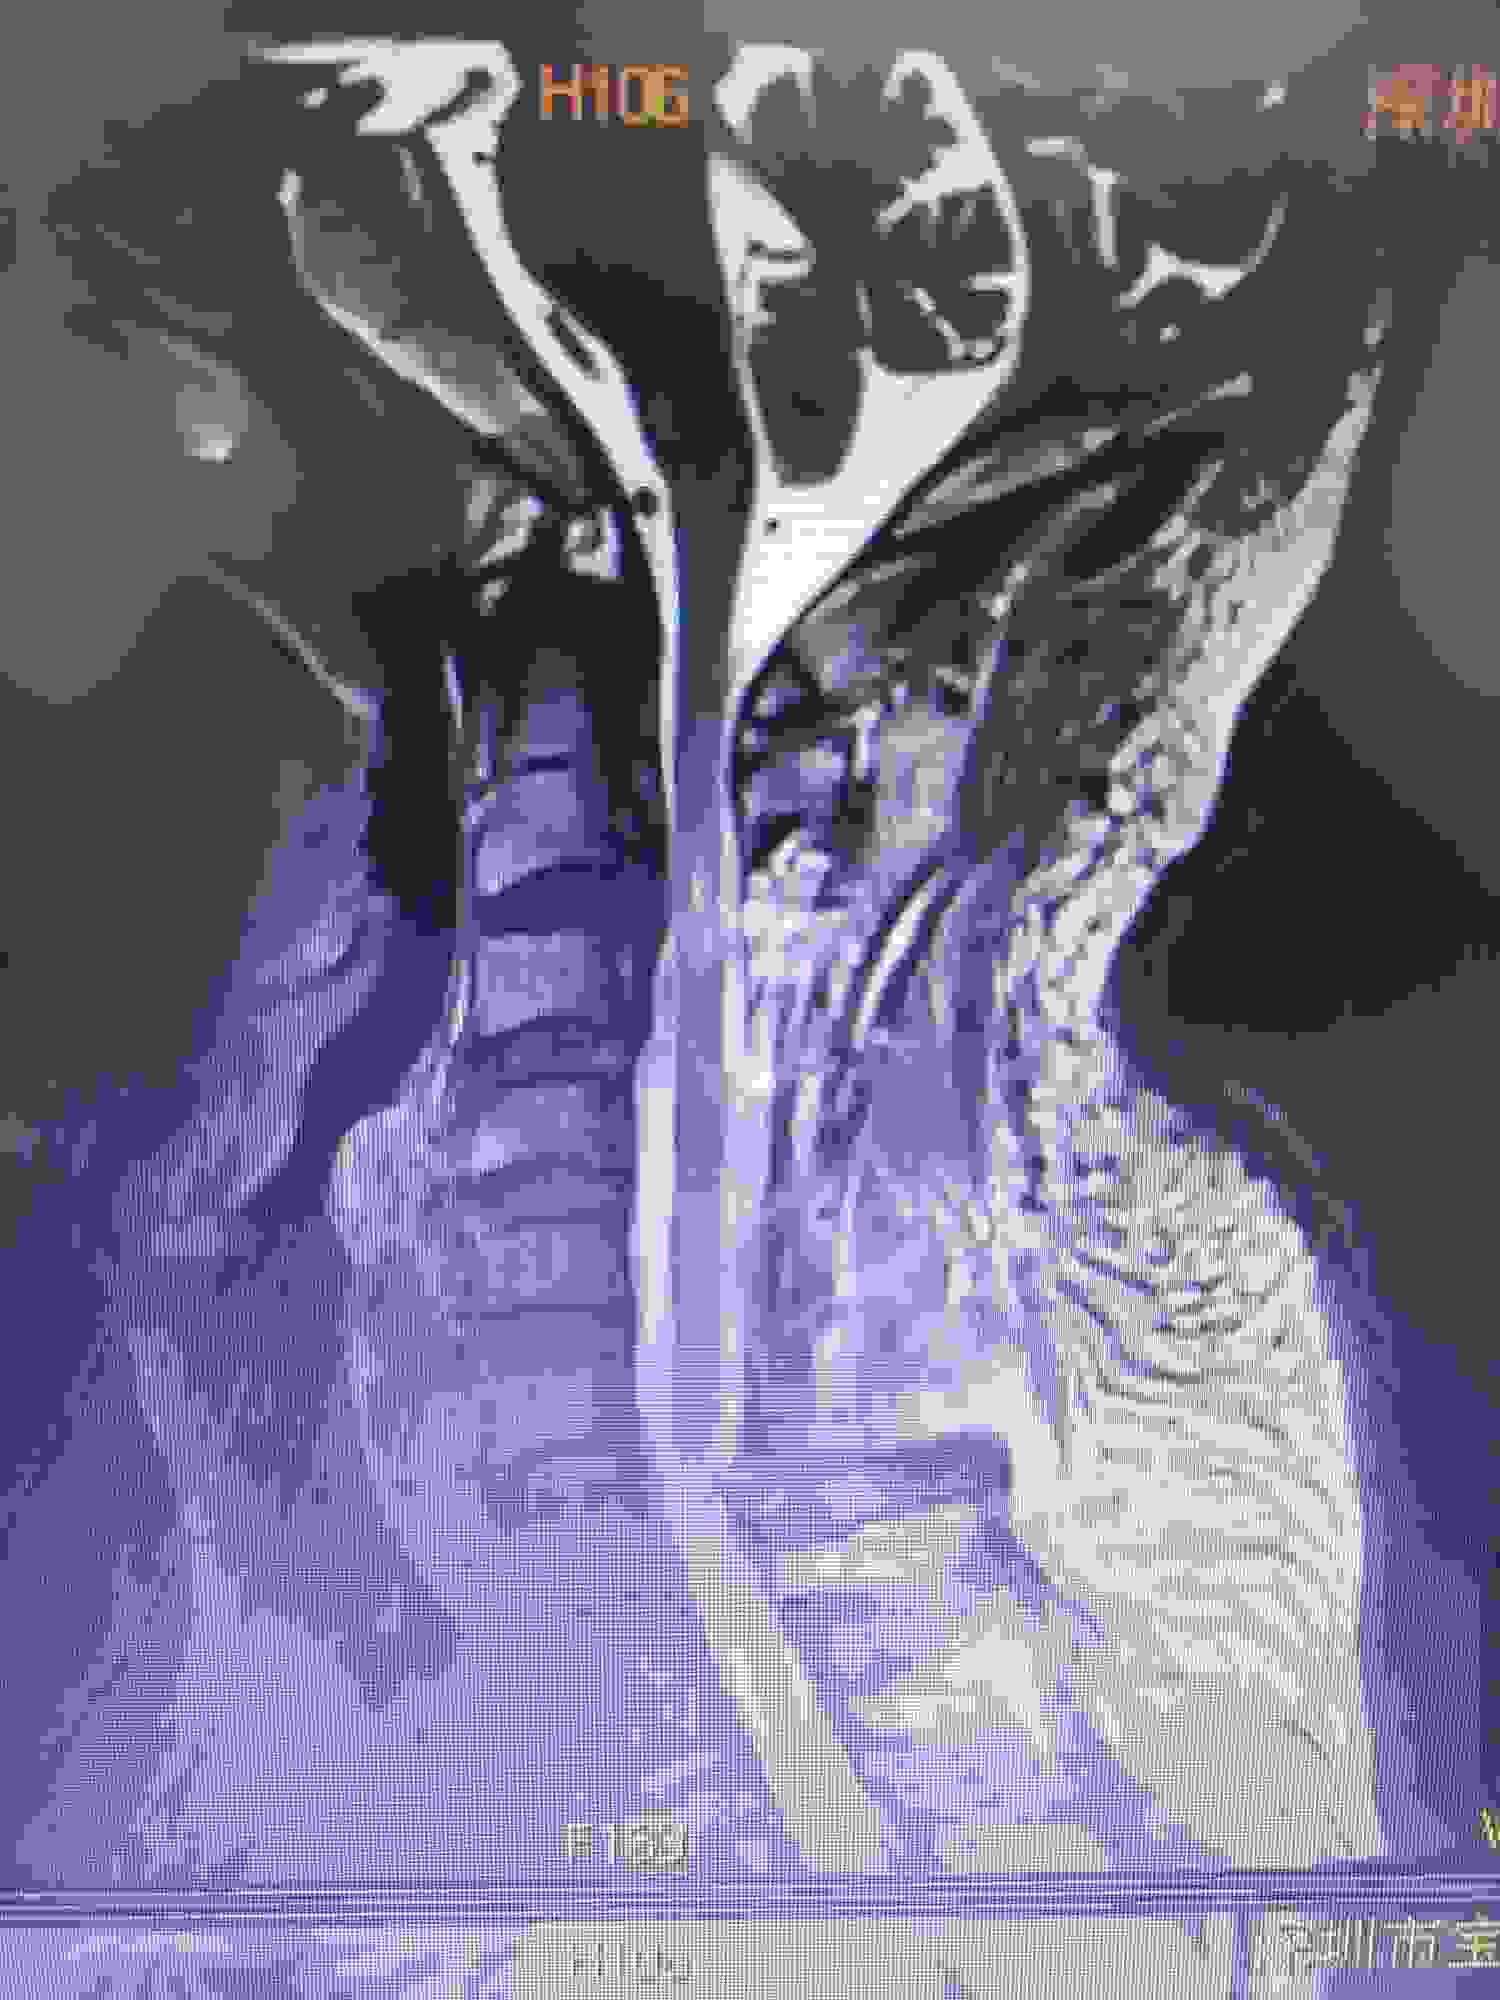

在颈椎2-3椎体后缘处有很大的骨赘(也就是骨质增生),医学上叫后纵韧带骨化(OPLL)。估计是这造成椎管变窄,压迫脊髓,外伤后加重,引起症状。又做了核磁共振。

在颈椎2-3处脊髓明显受压迫,受到损害。这种压迫不会因为保守治疗而解除,现在为了抢救脊髓功能,不至于造成上肢终身瘫痪。手术是唯一的选择。

术前和术后对比在颈2-3压迫最明显处,压迫得到了解除。术后双侧上肢的功能也从一级恢复到了基本正常5级弱。